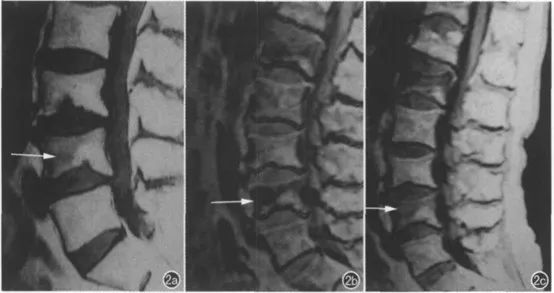

椎体骨折作为临床上比较常见的疾病,依据骨质疏松、外伤、肿瘤等因素可划分性良性骨折和恶性骨折。传统采用MRI进行鉴别虽然具有一定的效果,但仍然有部分患者的常规T1、T2像上表现类似,难以有效鉴别。化学位移成像能够定量分析组织中的脂肪,有助于椎体骨折的良恶性诊断。恶性椎体骨折的骨髓被逐渐被肿瘤细胞代谢,反相位不会表现出明显的信号减低;而良性椎体骨折的骨髓则主要是被水肿浸润,骨髓中脂肪成分被保留,可出现明显的信号降低(图4)。此外,化学位移成像还可用于骨髓局灶性病变的鉴别、骨髓水肿区小梁间骨折的检出、反映椎体脂肪含量变化等方面。

图4:一例L4椎体骨质疏松压缩性信号异常。a) T1WI示L1椎体前部呈略低信号,椎体后部为正常骨髓信号;b) 反相位图示L1椎体前部呈低信号;c) 同相位图示L1椎体前部呈略高信号。